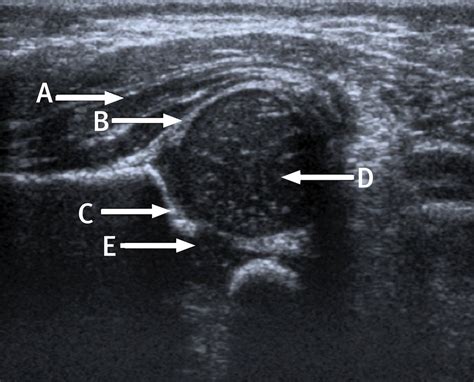

The results of an Infant Hip Ultrasound are interpreted by a radiologist or orthopedic specialist who is trained in pediatric imaging. The images are evaluated for several key factors, including:

• The shape and depth of the acetabulum

• The position of the femoral head within the acetabulum

• The presence of any abnormalities or dislocations